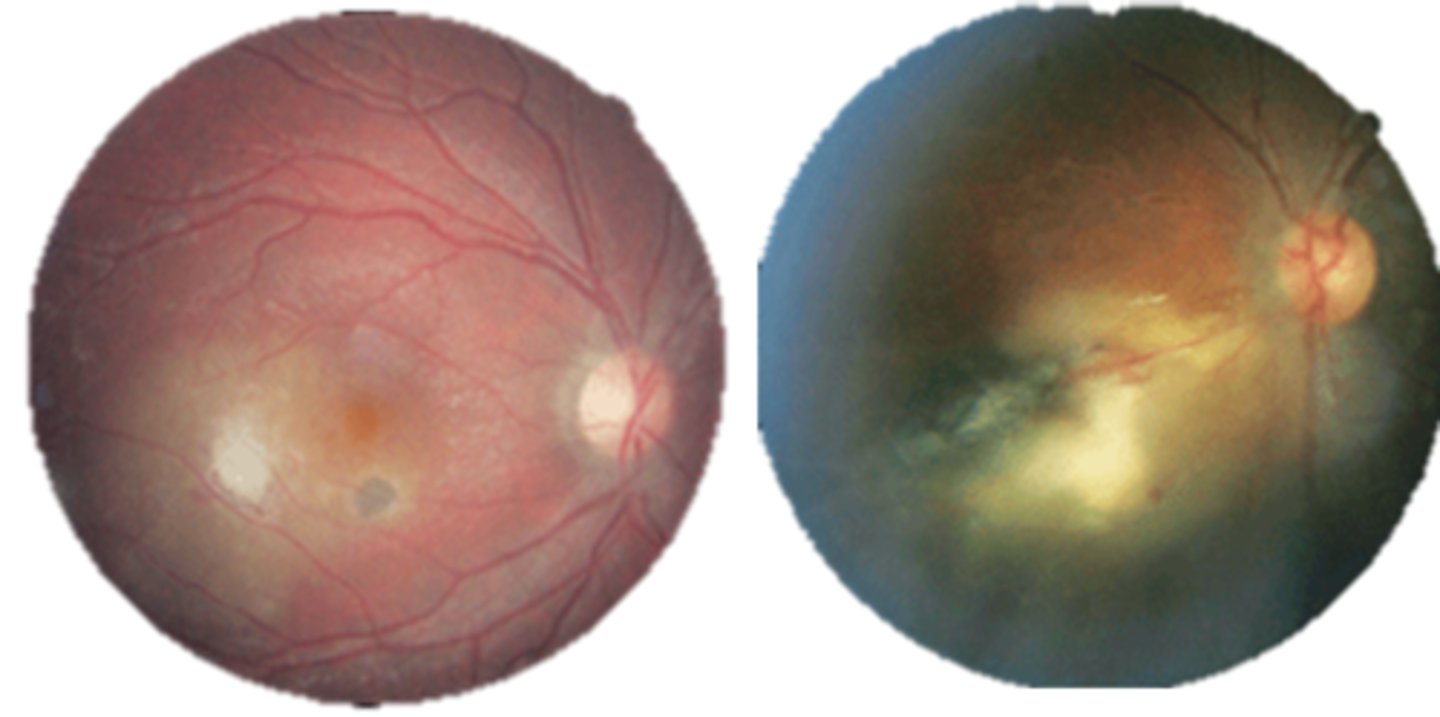

What finding of toxoplasmosis is seen in A/B?

retinitis turns into hazy scar with nerve pallor

What finding of toxoplasmosis is seen in C/D?

scarring overtime with VA loss/scotoma